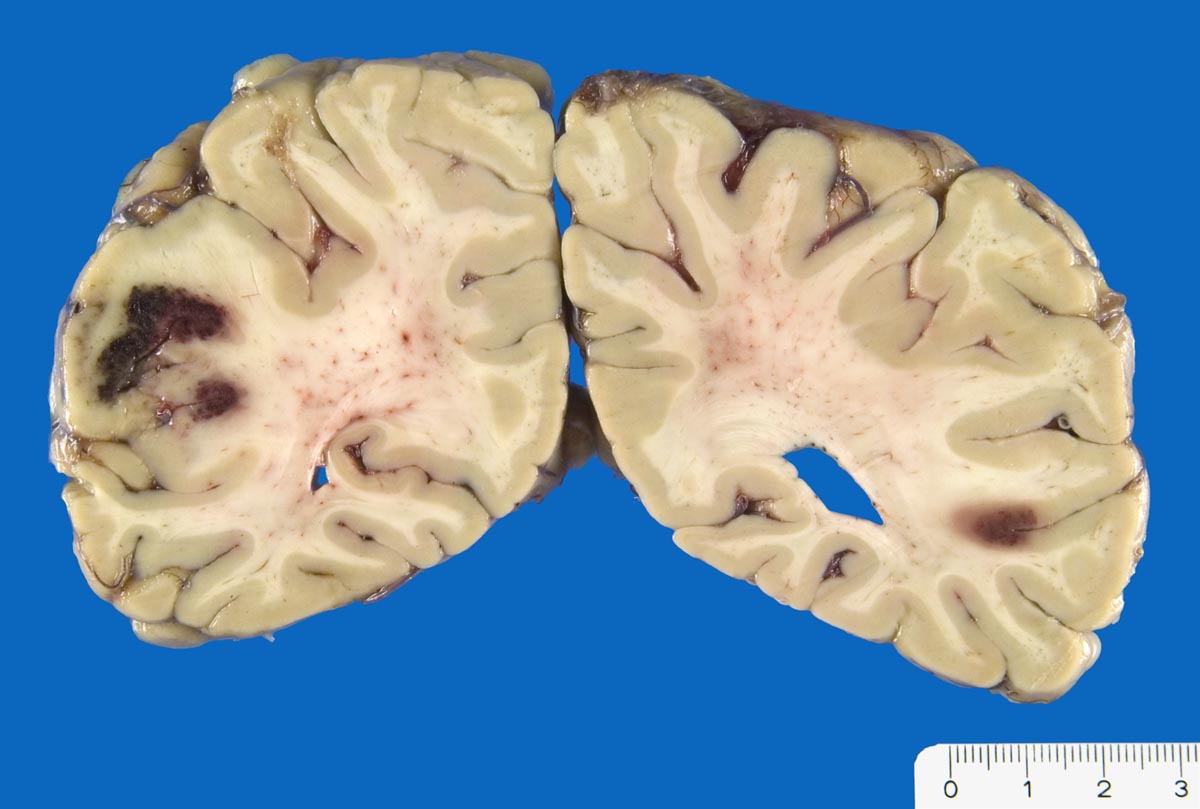

Sekundär hämorrhagische Enzephalomalazie

vaskulär / Durchblutungsstörung

Hirn

Nicht ganz frische anämische Infarkte mit sekundärer Einblutung.

Arterielle Hypertonie. V.a. ischämischen Insult. Akutes Delir. CCT: links posteriore Hypodensität, kein Hemisyndrom

Koronare Herzkrankheit, St.n. Myokardinfarkt vor 11 Jahren.

Plötzlicher Tod